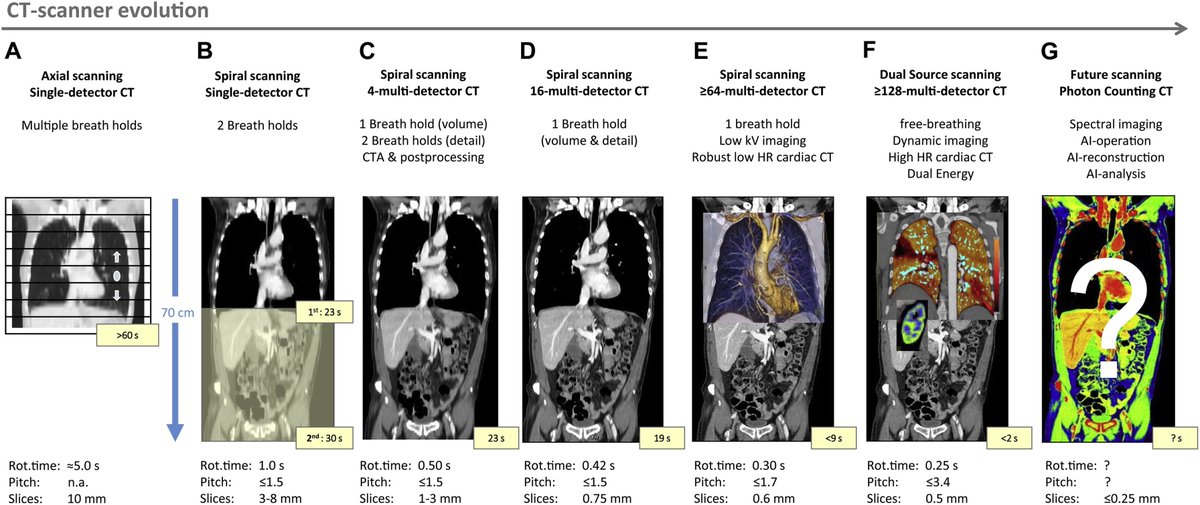

أدت التطورات المستمرة في تقنية التصوير المقطعي المحوسب إلى أوقات مسح أسرع وتحسين جودة الصورة. يلعب متخصصو الهندسة الطبية الحيوية دورًا مهمًا في تحسين وصيانة أجهزة التصوير المقطعي المحوسب لضمان أدائها بدقة وموثوقية عالية في إعدادات الرعاية الصحية. 🌐🛠️